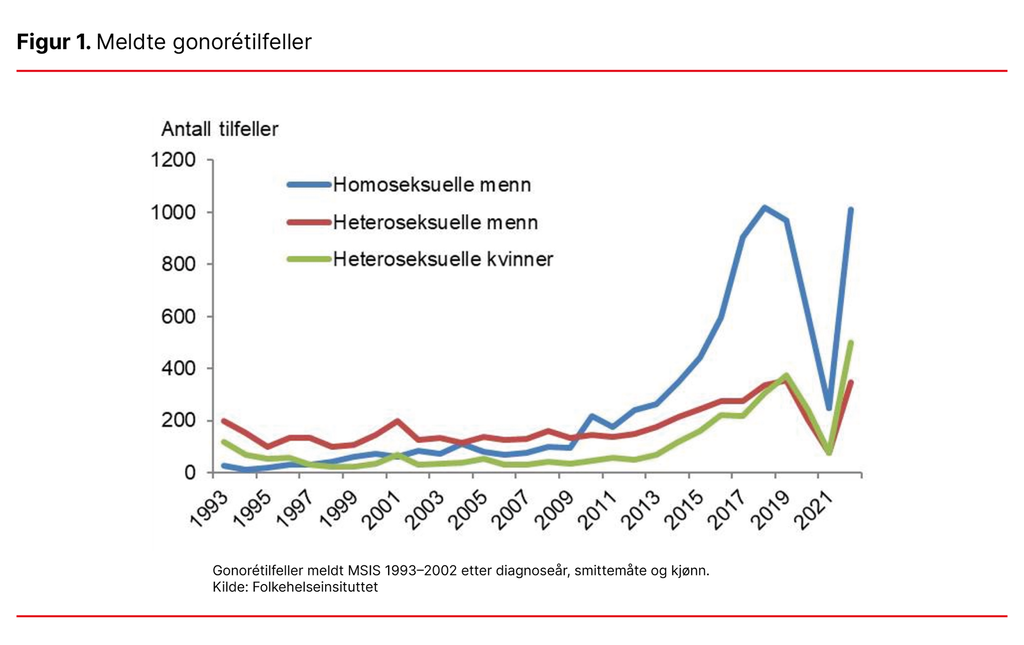

Gonoré ble nesten utryddet i Norge med kun et par hundre tilfeller årlig på slutten av 90-tallet og starten av 2000-tallet. Fra 2010 økte gonoré betydelig blant menn som har sex med menn. For menn som har sex med kvinner, og kvinner som har sex med menn eller kvinner, så man en økende tendens fra 2012 (se figur 1) (4).

Økningen skyldtes trolig redusert bruk av kondom på grunn av mindre frykt for hiv. Under covid-pandemien sank forekomsten, men nå ringer alarmklokkene på nytt. Gonoré er på fremmarsj igjen, og denne gangen spesielt blant unge kvinner. I starten av mars 2023 er antall smittede kvinner nesten fem ganger så høyt som det totale antall smittede kvinner i hele 2003. Og russetiden har ikke engang begynt (se tabell 1) (5).